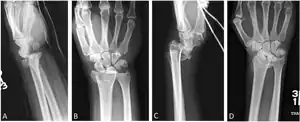

Additional images

Lateral projectional radiograph of the same fracture

Barton's and reverse Barton's